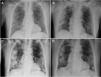

Se presenta el caso de un varón de 72 años, hipertenso, dislipidémico y trasplantado renal desde 2012. Mantenía tratamiento inmunosupresor con tacrolimús y everolimús, y presentaba una cifra de creatinina basal de 1,43mg/dl. El paciente acudió a urgencias refiriendo malestar general y cefalea de 3días de evolución. Presentaba cifras tensionales normales, temperatura axilar de 37°C y saturación de oxígeno (SatO2) del 92% respirando aire ambiental. En la radiografía de tórax presentaba infiltrados pulmonares bilaterales de perfil intersticial (fig. 1A) y a nivel analítico destacaba un fracaso renal agudo (valores de creatinina y urea: 2,52mg/dl y 77mg/dl, respectivamente) y una elevación de los niveles de tacrolimús (15,1 ng/ml) respecto a su último control. La determinación de PCR del exudado nasofaríngeo resultó positiva para SARS-CoV-2. Se decide ingreso, iniciándose tratamiento con hidroxicloroquina, azitromicina y lopinavir/ritonavir junto con ceftazidima y glucocorticoides (tabla 1), suspendiéndose el tratamiento inmunosupresor que tomaba el paciente.

Tras 5días de ingreso, en los que la evolución clínica fue favorable, con disminución de los parámetros inflamatorios a nivel analítico y una normalización de la función renal, presentaba un aumento en los niveles de tacrolimús (29,31 ng/ml), normalizándose tras 4días. Se realizó una nueva radiografía en la que se descartó la presencia de progresión (fig. 1B), decidiéndose alta hospitalaria y reinicio del tratamiento inmunosupresor previo a dosis habituales.

Siete días más tarde acudió nuevamente a urgencias refiriendo fiebre los días previos con aumento progresivo de la sensación disneica acompañada de síndrome miccional. Se realizó una radiografía de tórax donde presentaba empeoramiento con respecto a la previa (fig. 1C). La determinación analítica reflejó leucocitosis (16,4 miles/μl) con linfopenia (0,6 miles/μl) y elevación de reactantes de fase aguda (PCR 7,6mg/dl, dímero D 886 μg/l y procalcitonina 3,88 ng/ml). Se inició tratamiento con IgIV, acompañado de linezolid y meropenem, y se cursó ingreso (tabla 1), suspendiéndose nuevamente el tratamiento inmunosupresor previo.

Completaron 5días de tratamiento con IgIV sin presentar reacciones adversas y con una marcada mejoría a nivel clínico, con desaparición de la disnea y mejoría radiológica (fig. 1D), lo cual permitió el alta hospitalaria precoz al sexto día.